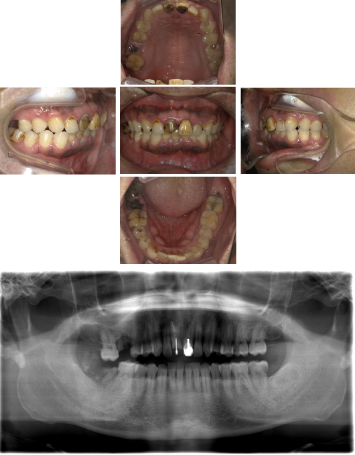

50代 インプラント治療(右上3左上3のみGBR)

| 年代・性別 | 50代・男性 |

|---|---|

| 主訴 | 入れ歯が合わず毎日ヨーグルトしか食べることができないので、しっかり咬めるインプラントにしたい。 |

| 部位 | 右下⑦⑥5④ 上顎③2①①2③ 左下67 |

| 治療期間 | 約9ヶ月 |

| 費用 | ¥4,273,500(税込) |

| 副作用・リスク |

|